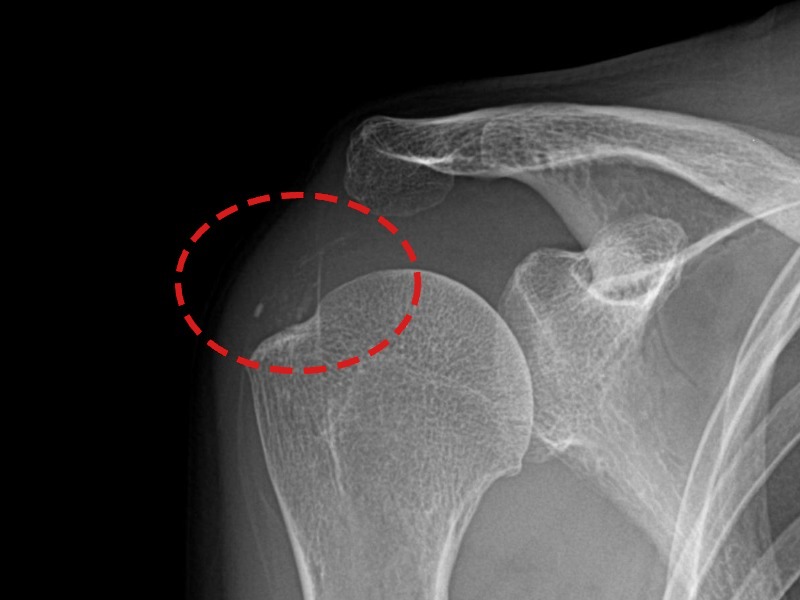

[촬영시기:21.08.30~21.09.09]

[석회분쇄흡입술] 우측 어깨 통증으로 밤잠을 못 이루고 팔을 올리기 어려워진 30대 여성 환자로, X-ray에서 우측 극상근건 내 석회 침착이 확인되어 석회분쇄흡입술을 시행하였습니다.